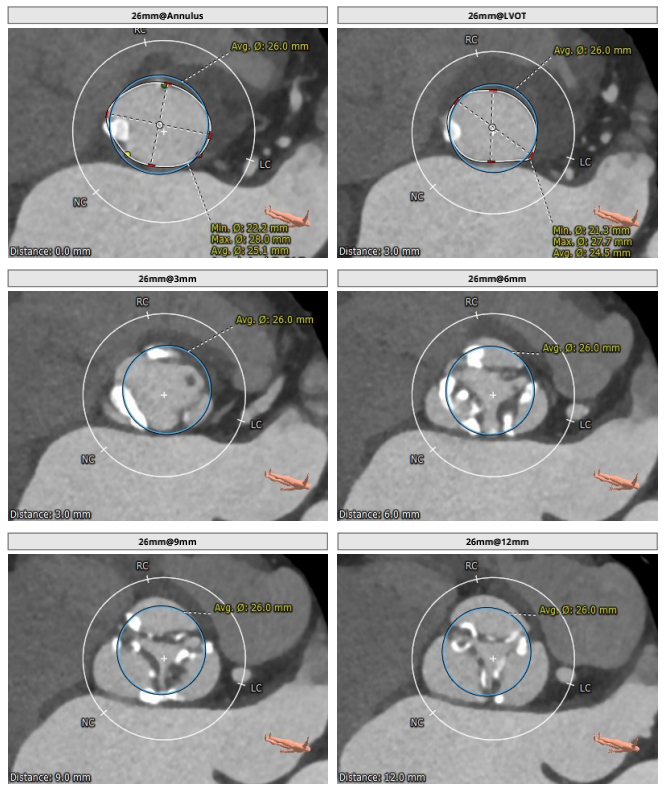

2021年12月17日,四川省人民医院结构性心脏病团队成功挑战高龄主动脉瓣严重狭窄合并弥漫钙化,顺利完成SAPIEN 3瓣膜植入。在团队成员紧密配合下,克服患者入路狭小弥漫钙化病变,充分利用SAPIEN 3瓣膜的优异性能,顺畅完成过弓、跨瓣及释放操作,手术取得圆满成功。这也是四川省人民医院首例应用SAPIEN 3瓣膜完成的TAVR手术。